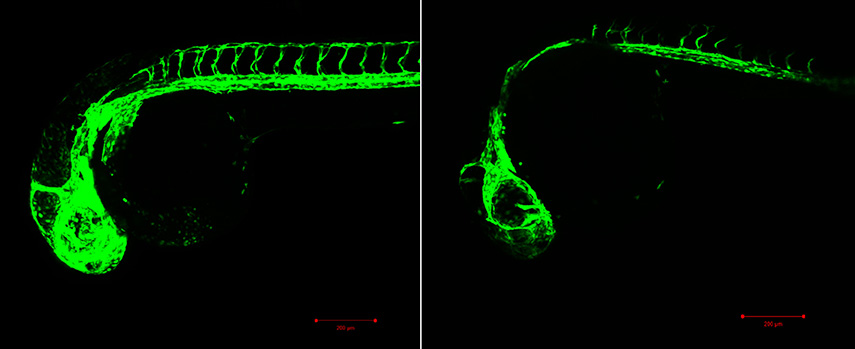

Confocal images show the lateral side of the anterior region of a 2-day-old transgenic Tg(Fli:EGFP) zebrafish larva control WT on the left and morphant on the right. The green structure represents the blood vasculature in the head and the intersegmental vessels. This image was captured using the LSM 880 confocal microscope at the core facility using the 488 laser and the 10x objective. Scale bar is 200 micrometers (µm).